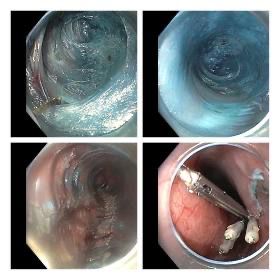

Successful POEM for Achalasia Cardia via Anterior Approach

We are pleaed to announce that last week at GI-One Hospital, we successfully performed a Per Oral Endoscopic Myotomy (POEM) using the Anterior approach in a patient with sigmoid esophagus. The procedure went smoothly, and the patient was discharged on postoperative day 2.

With this case, we have now completed 40 POEM procedures at our center — all previously via the Posterior approach, including patients with prior Laparoscopic Heller’s myotomy, with consistently excellent outcomes.

🔹 Posterior POEM: Technically easier, as the prominent spine provides a clear landmark in a dilated esophagus.

🔹 Anterior POEM: More challenging — multiple vascular indentations and pulsations demand careful preservation of longitudinal muscles during myotomy. Scope manipulation is also trickier, particularly during mucosal closure.